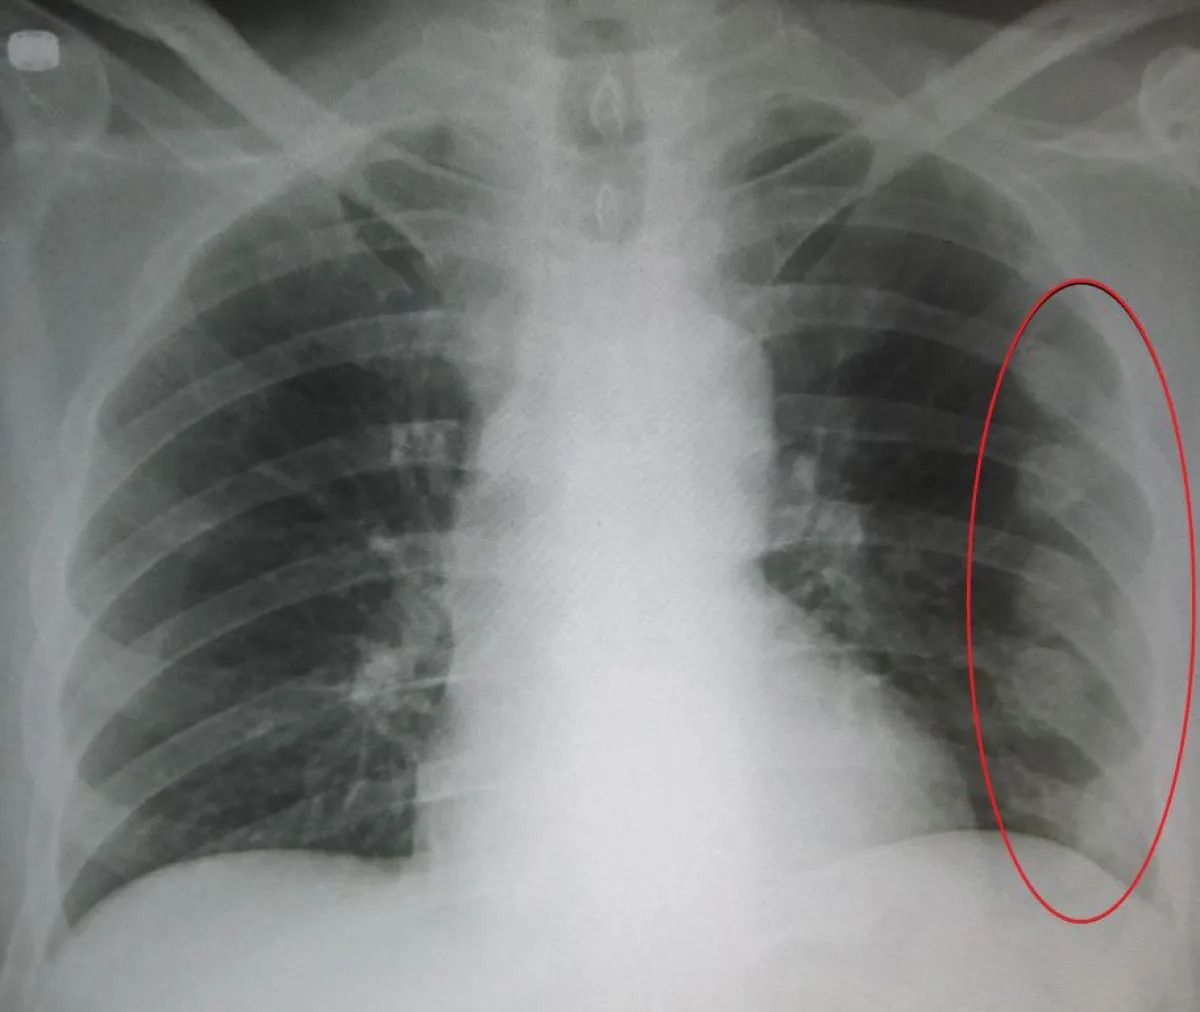

فيما بعد، ومع تواصل سعال الفتاة العشرينية الغريب، أدرك الأطباء أن ما تعانيه كشف عن عارض صحي أكثر خطورة من مجرد نوبة ربو. ومع استمرار سعالها الشديد لأيام أخرى، ومعاناتها من ألم في جانب صدرها الأيسر، وبعد فحوصات مكثفة، اكتشف الأطباء أمراً صادماً للغاية، وهو الألم كان بسبب عدد من الأضلاع المكسورة لديها. والصدمة الأخرى التي أذهلت الأطباء بعد فحوصات جديدة أجريت لها، أن كثافة عظامها كانت أقل بكثير من متوسط ما هو عليه عند النساء الصينيات.